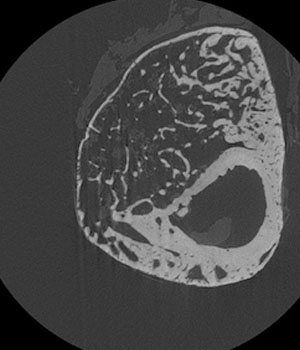

A 2D X-ray (microCT) image of a cross section of a mouse’s tibia (solid, bottom right). The outer portions are referred to as the callus and contain the healing bone along with cartilage and cells such as inflammatory and mesenchymal stem cells. When UC2288 is injected at the site of fracture, increased volume is observed in the callus. Premnath aims to spur mesenchymal stem cells, found in the bone marrow and lining of the bone, to become osteogenic cells that will contribute bone regeneration.